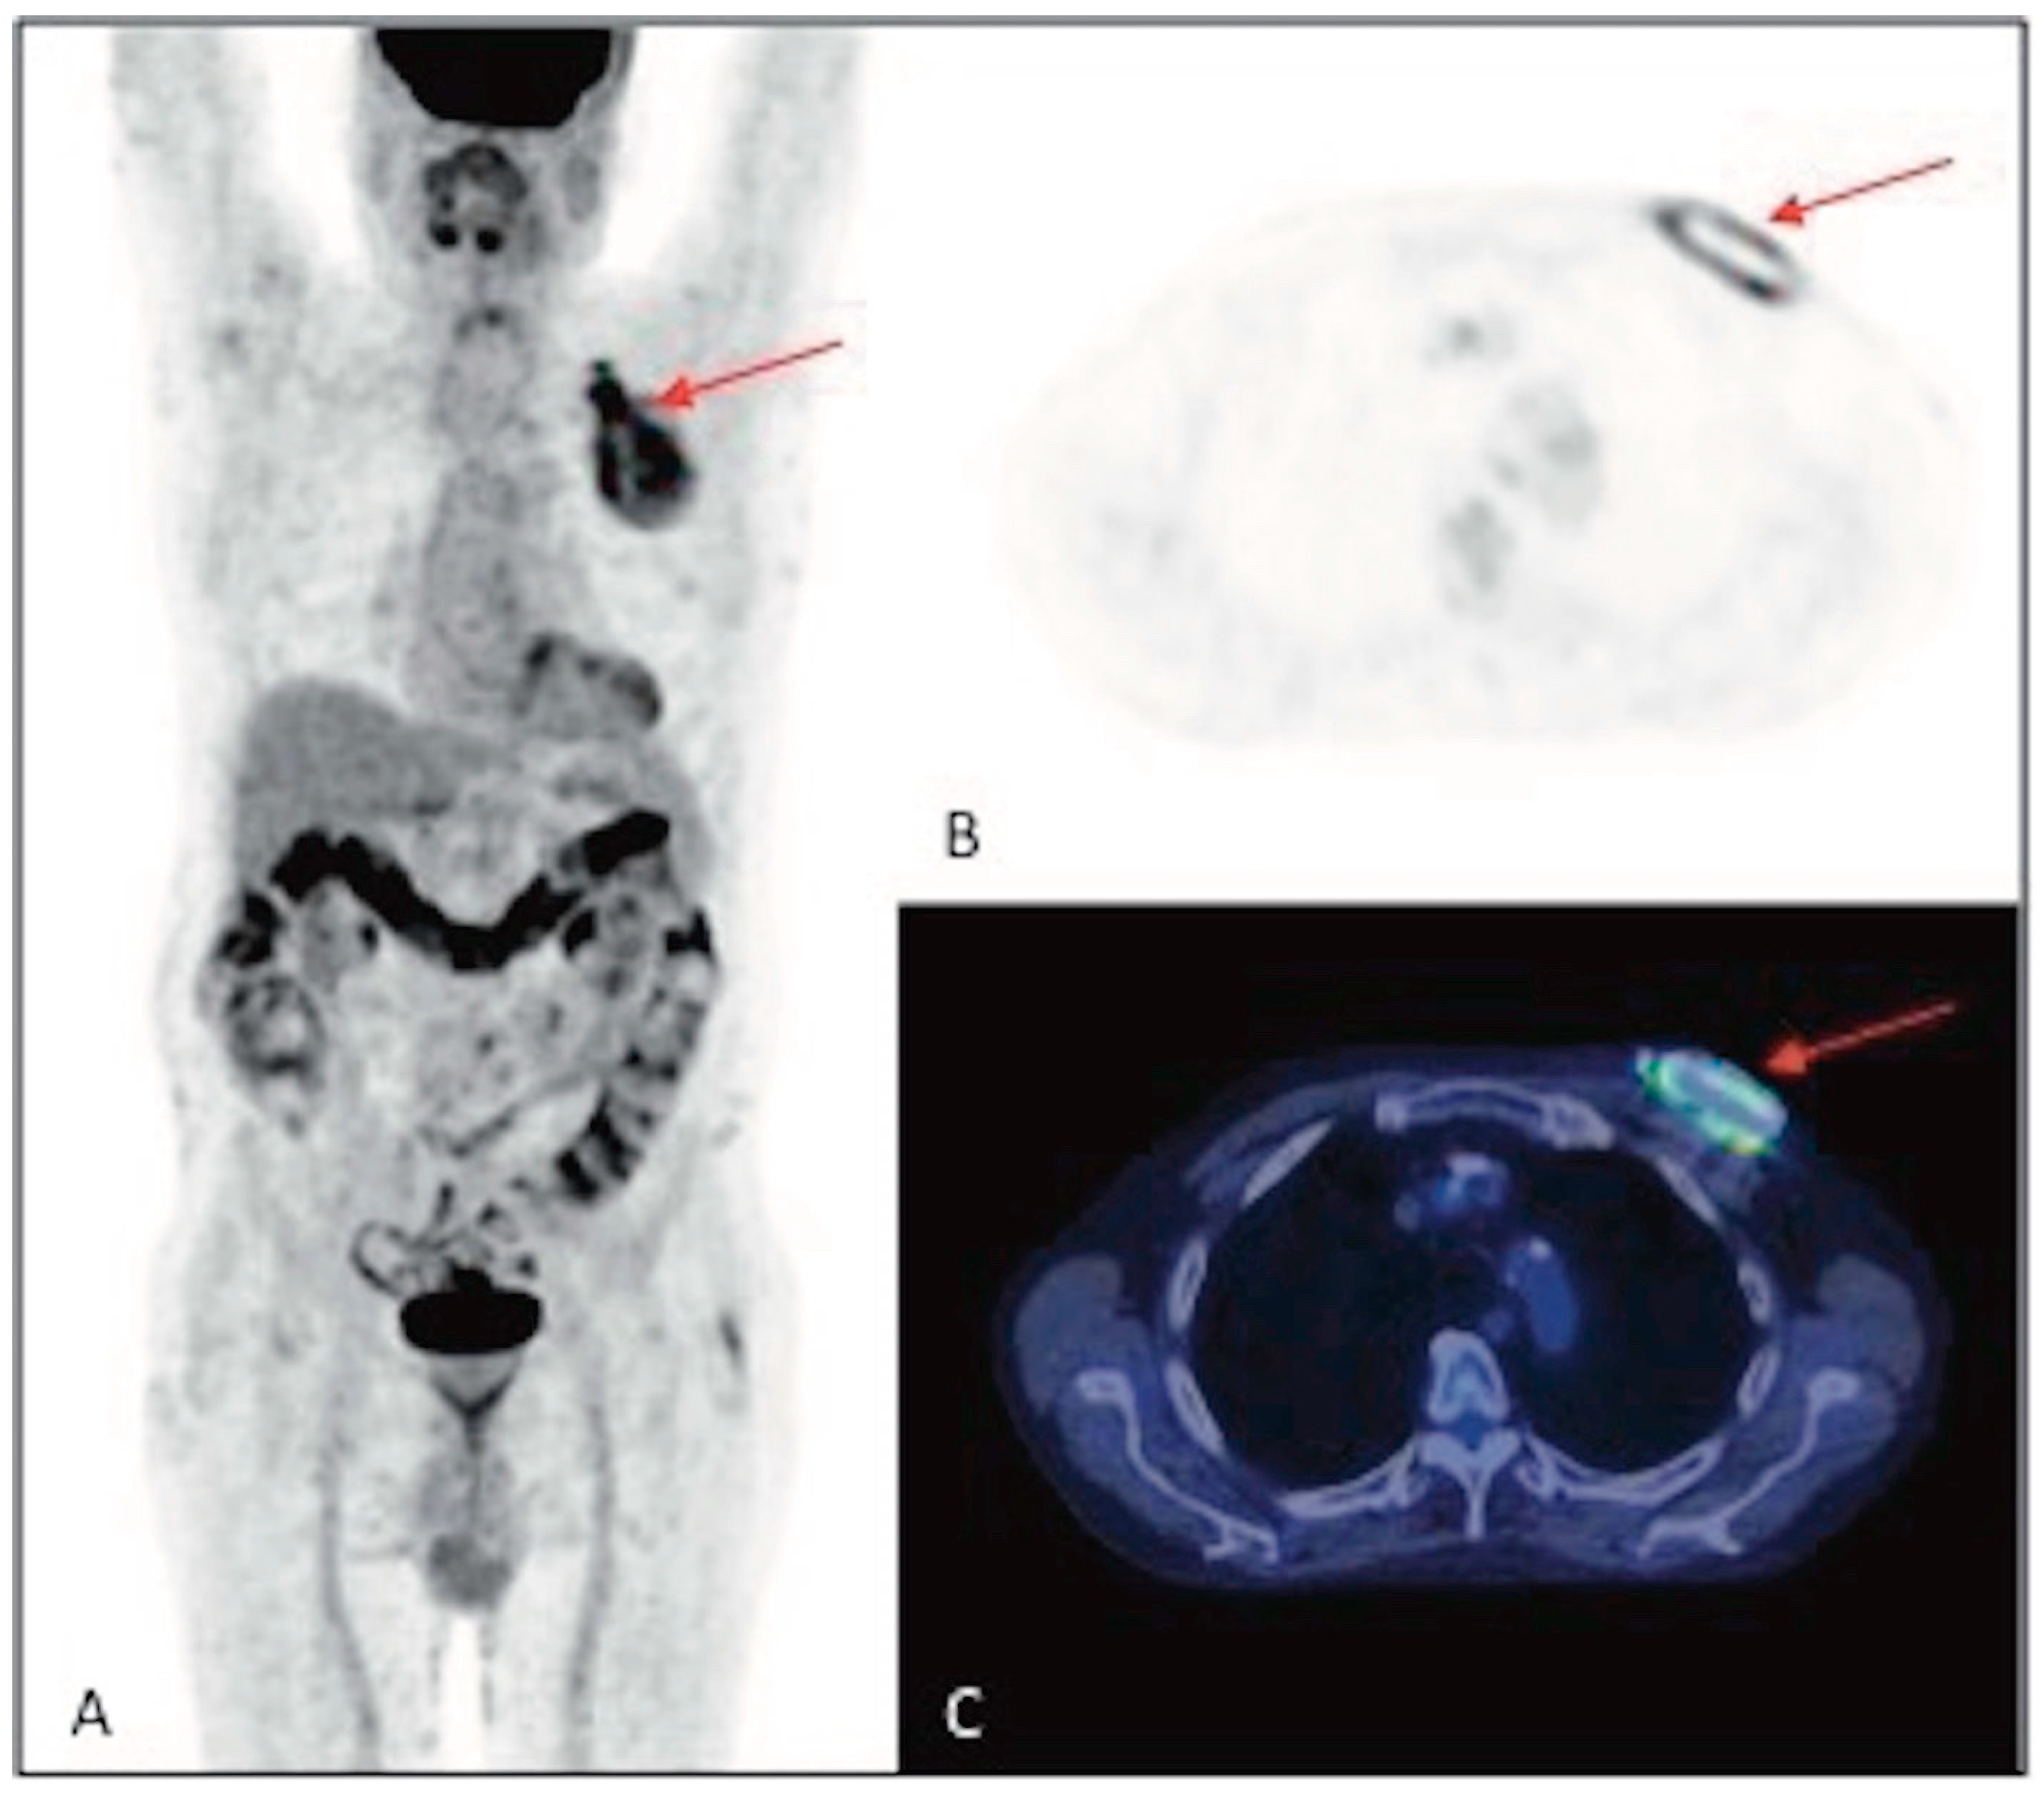

3.2. Results of the 18F-FDG PET/CT Examination Analysis